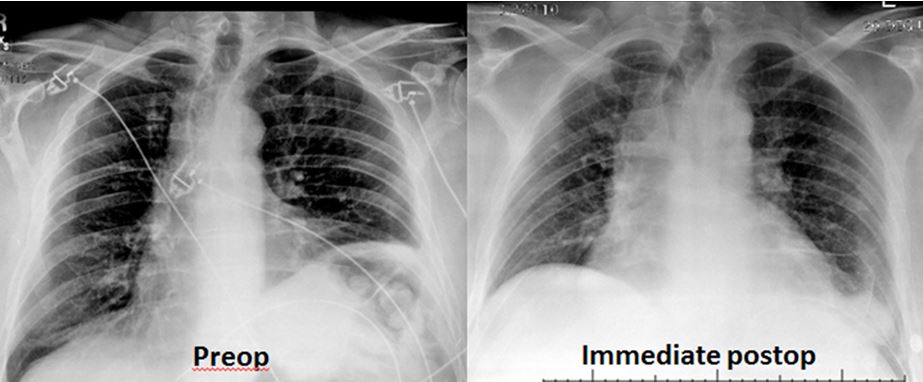

Smoking is the primary cause of emphysema which makes it a preventable illness. Diaphragm weakness due to medical intervention most commonly occurs as a result of physical trauma to the phrenic nerves or diaphragm muscle. Surgical treatment is an option for more advanced cases or if breathing becomes so impacted daily life is affected.

You may not need any treatment. Depending on the severity of injury to the diaphragm some doctors recommend non-surgical options to treat the breathing issues associated with diaphragm weakness and paralysis.

The rise in intraabdominal pressure further increases intrathoracic and lung volume by pushing the lower rib cage outward. In severe cases when there is no simple treatment that can relieve dyspnea your doctor may prescribe morphine. Diaphragmatic dysfunction caused by transverse myelitis or leukemic infiltration of the cervical spinal cord in a patient with leukemia and shortness of breath. Diaphragmatic plication a surgical procedure that pulls the diaphragm down by introducing a repeated series of continuous sutures across the diaphragm and pulling the muscle taut. A bedside fan or open window with a breeze are also simple but very effective treatments to lessen dyspnea. Depending on the severity of injury to the diaphragm some doctors recommend non-surgical options to treat the breathing issues associated with diaphragm weakness and paralysis. P E Pulmonary embolism.